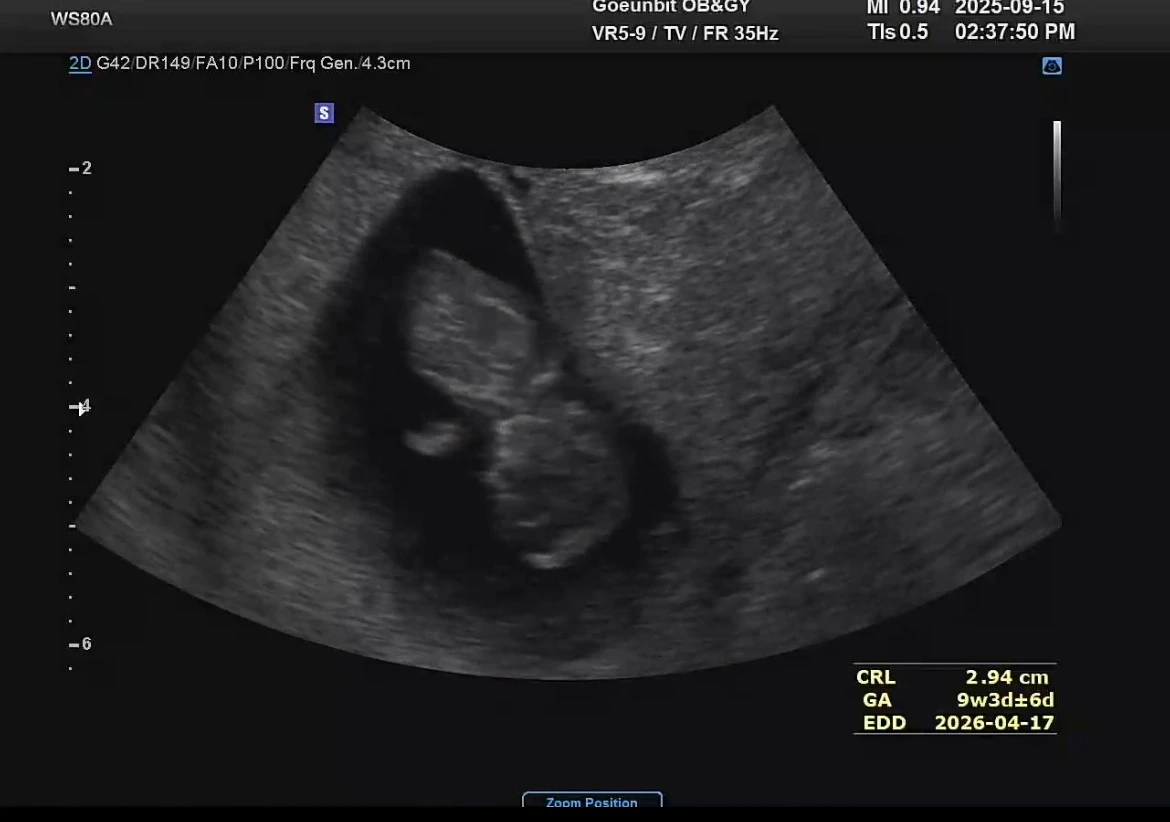

하루하루 반복되는 일상은 똑같은데 활동성이 많이 줄어들다보니 맥아리가 없이 쳐지는 기분이 든다. 제일 귀엽다는 젤리곰 초음파를 보고 와도 설레는 마음이 지속되진 않는다.

이 두가지가 날 갉아먹는것 같다. 아이는 3센티밖에 되지 않는데 자잘한 먹덧으로 야금야금 살이 불어나고 있다. 배뿐아니라 가슴도 커지고 있어서 가지고 있는 옷들이 답답해 지거나 잠기지 않는 현상이 발생하고 있다. 아니 9주차 부터 이러면 나머지 기간은 어떻게 입고 살라고?

그래도 아기는 자신의 발가락을 뽐내며 내 뱃속에서 데굴데굴 잘 굴러 다니고 있다. 막되먹는 생각을 하는 엄마에 비해 퍽 대견한 행보다.